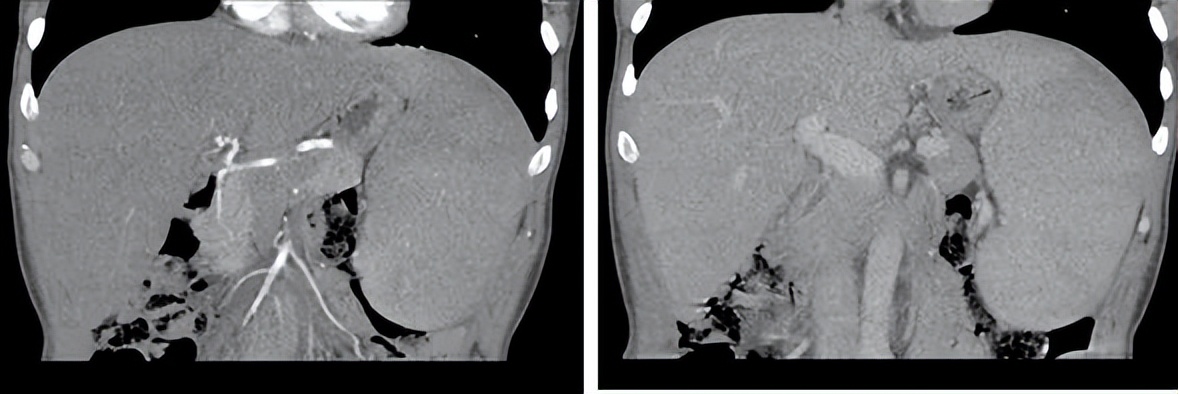

完善腹部CT提示:①肝脏体积增大,肝右叶邻近胆囊底区类圆形低密度影,增强后未见明显强化,多系肝囊肿可能,其他不除外;②脾大,增强后脾脏强化欠均;③门脉直径增宽(图1)。2016年12月22日行骨髓穿刺示:环片一周易见利杜氏小体,异型淋巴细胞病(图2)。肝穿刺活检:肝组织结构大致正常,肝窦吞噬细胞增多,少数肝细胞及吞噬细胞内见较多颗粒样微生物沉积,考虑黑热病或组织胞浆菌病(图3)。

图 1.增强CT图像:动脉期(左),门脉期(右)

本例患者以“皮肤黄染,发热、盗汗”为主要症状,既往有*藏西**阿里地区居住史,同时伴不明原因的反复发热,查体发现有脾大,肋缘下四横指;腹部CT提示肝脏体积增大、门脉直径增宽;血常规示三系减少、低白蛋白、白球比例倒置、CRP升高、梗阻酶升高、肝酶升高等。在排除肝硬化、结核感染、自身免疫等其他可能的原因后,经骨髓穿刺和肝脏穿刺证实,考虑诊断为黑热病。